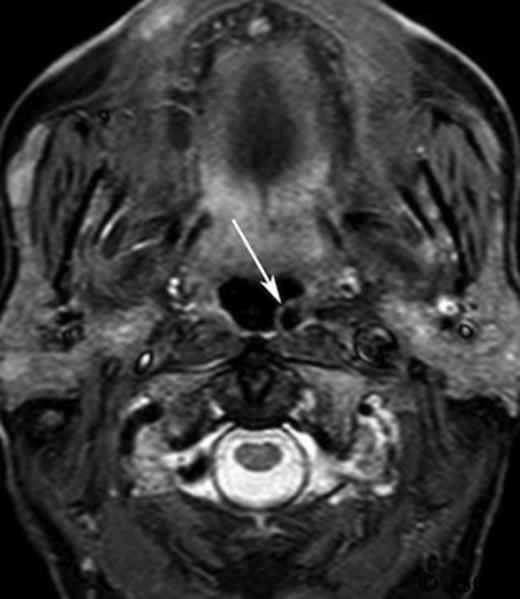

A CT scan, requested as part of his lymphoma follow-up, revealed asymmetrical fullness of the left nasopharynx due to a mass in the retropharyngeal space.(Figure 1) Owning to patient intolerance, nasoendoscopy was difficult in the clinic setting, and the nature of this swelling could not be properly determined. With the history of previous malignant disease, and the risk of recurrence or new disease being high, a biopsy was requested by the oncology team. However, since the CT imaging showed that the bulging mass could possibly be an artefact of a medially coursing left internal carotid artery (ICA), it was decided to perform a magnetic resonance imaging (MRI) prior to the biopsy. The MRI confirmed the ICA ectasia (often referred to as tonsillar loop) which manifested the asymmetry of the contour of the nasopharynx with prominence and fullness on the left just below the fossa of Rosenmuller.(Figure 2) There was no evidence of any mucosal abnormalities of nasopharynx or of the remainder of upper aerodigestive tract. No other pathological lesion was noted and the biopsy was cancelled.

Short inversion time inversion recovery (STRI) axial magnetic resonance imaging of the retropharyngeal region (arrow)